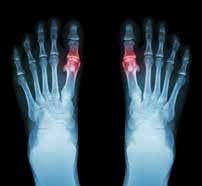

Fractures, Arthritis and More

The new facility will allow the doctors at SFISM to treat many ailments in-house, eliminating the need for a trip to the hospital. They diagnose and treat all foot, ankle and leg fractures in adults and children. They also treat foot and ankle arthritis and many cartilage injuries.